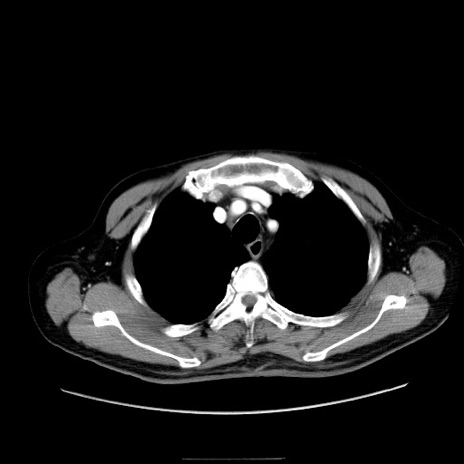

症例30(横断像)

【症例】80歳代男性

【主訴】臍周囲痛

【現病歴】約6時間前から臍下部痛が出現。次第に腹部膨隆・背部痛も生じてきたため来院。背部痛の場所は変化しない。

【身体所見】意識清明、BT 36.3℃、BP  131/87mmHg、P 87bpm、SpO2 100%(RA)、臍周囲自発痛・圧痛あり、反跳痛なし、自発痛部位に一致して板状硬あり、腹部膨隆、腸雑音減弱、CVA tenderness両側陰性。